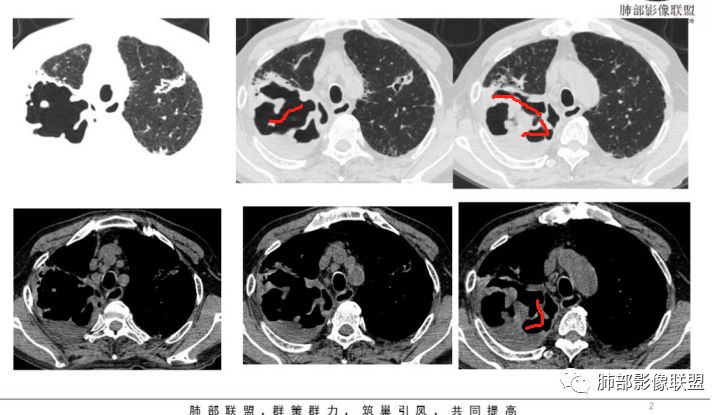

2.双肺多发病灶,主要集中在右肺,斑片影、结节影,条索影,支扩等等,右肺病灶胸膜下居多,密度偏高不均,偶见钙化。

3.右肺巨大空洞影。值得注意的是:

1)空洞内坏死相对彻底(未见絮状物或丝状物等)。

2)空洞壁密实,内外壁都清楚,这是慢性病灶特征之一。

3)内壁不规则,多呈不规则山脊样突入,这些“脊”等同于空洞壁的密实。尽管洞腔内蜿蜒不规则,但并未形成洞壁的膨隆样结节影,换句话说,外壁看不出分叶!

这种空洞更多见于结核!

4)空洞病灶内显示液平。提示伴有细菌感染等。

5)肺门纵隔未见肿大淋巴结。